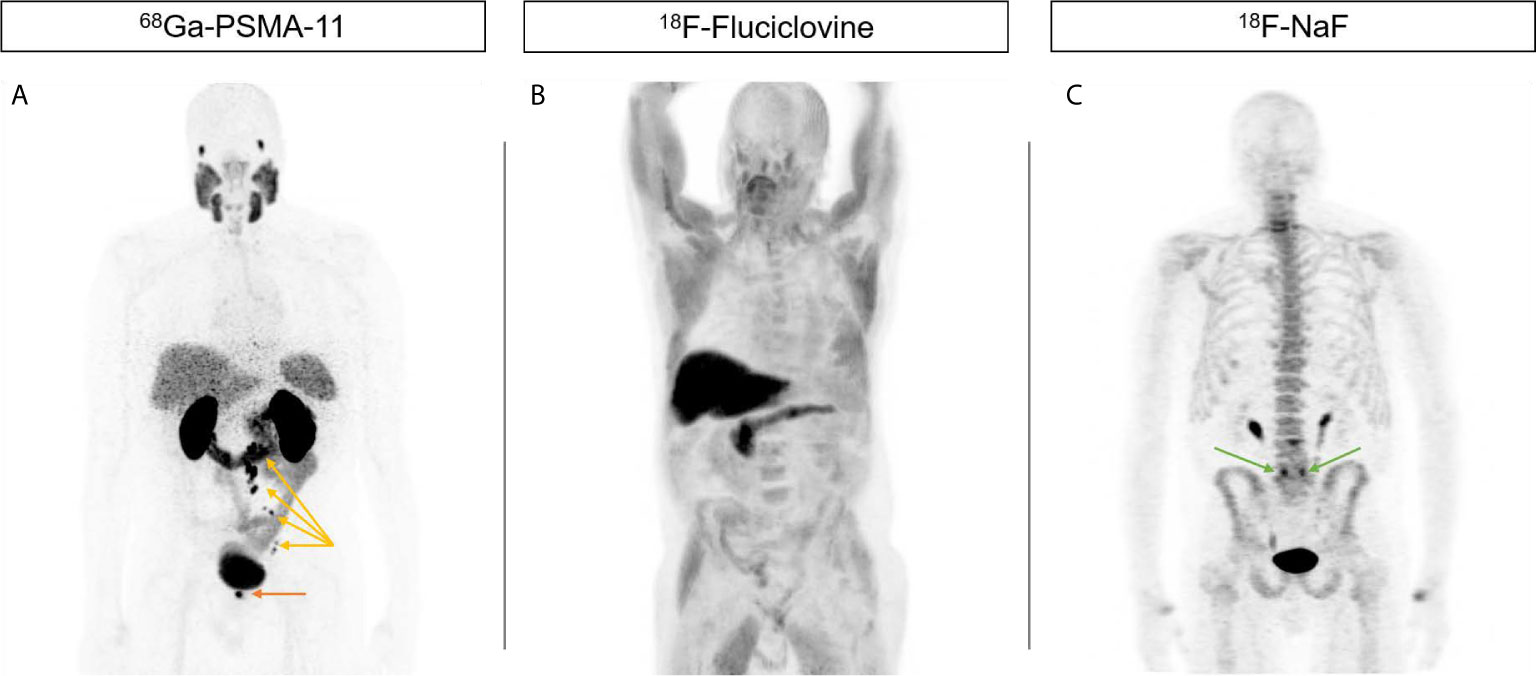

Prostate-specific membrane antigen (PSMA) tracers have increased sensitivity in the detection of prostate cancer, compared with conventional imaging. We assessed the management impact of 18F-DCFPyL PSMA PET/CT in patients with prostate-specific antigen (PSA) recurrence after radical prostatectomy (RP) and report early biochemical response in patients who underwent radiation treatment. Methods: One hundred patients were enrolled into a prospective study, with a prior RP for prostate cancer, a PSA of 0.2–2.0 ng/mL, and no prior treatment. All patients underwent diagnostic CT and PSMA PET/CT, and management intent was completed at 3 time points (original, post-CT, and post-PSMA) and compared. Patients who underwent radiotherapy with 6-mo PSA response data are presented. Results: Ninety-eight patients are reported, with a median PSA of 0.32 ng/mL (95% CI, 0.28–0.36), pT3a/b disease in 71.4%, and an International Society of Urological Pathology grade group of at least 3 in 59.2%. PSMA PET/CT detected disease in 46.9% of patients, compared with 15.5% using diagnostic CT (PSMA PET, 29.2% local recurrence and 29.6% pelvic nodal disease). A major change in management intent was higher after PSMA than after CT (12.5% vs. 3.2%, P = 0.010), as was a moderate change in intent (31.3% vs. 13.7%, P = 0.001). The most common change was an increase in the recommendation for elective pelvic radiation (from 15.6% to 33.3%), nodal boost (from 0% to 22.9%), and use of concurrent androgen deprivation therapy (ADT) (from 22.9% to 41.7%) from original to post-PSMA intent because of detection of nodal disease. Eighty-six patients underwent 18F-DCFPyL–guided radiotherapy. Fifty-five of 86 patients either did not receive ADT or recovered after ADT, with an 18-mo PSA response from 0.32 to 0.02 ng/mL; 94.5% of patients had a PSA of no more than 0.20 ng/mL, and 74.5% had a PSA of no more than 0.03 ng/mL. Conclusion: 18F-DCFPyL PET/CT has a significant impact on management intent in patients being considered for salvage radiotherapy after RP with PSA recurrence. Increased detection of disease, particularly in the pelvic lymph nodes, resulted in increased pelvic irradiation and concurrent ADT use. Early results in patients who are staged with 18F-DCFPyL PET/CT show a favorable PSA response.

PSMA-targeted radiotracer pinpoints metastatic prostate cancer

Prostate-specific Membrane Antigen PET in Prostate Cancer